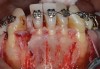

Fig 9. SFOT intraoperative surgical photograph; note the correlation of the CBCT scan in Fig 7 with the surgical findings, confirming the lack of blood supply even after completion of corticotomies.

Figure 9